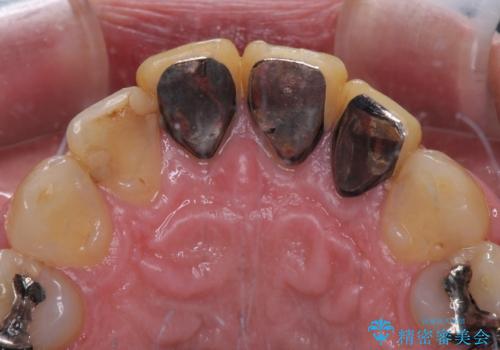

- 黄ばんだ前歯や目立つ奥歯の銀歯をきれいにしたいとのことで来院された患者様です。

欠損している歯や、割れてしまって抜歯の必要な歯などがあり、咬合力が強いため欠損部はインプラント補綴を前提に治療を行うこととしました。

小さい修復物の銀歯が装着されている歯はセラミックインレーにて、その他はオールセラミッククラウンにて補綴治療を進めることとしました。